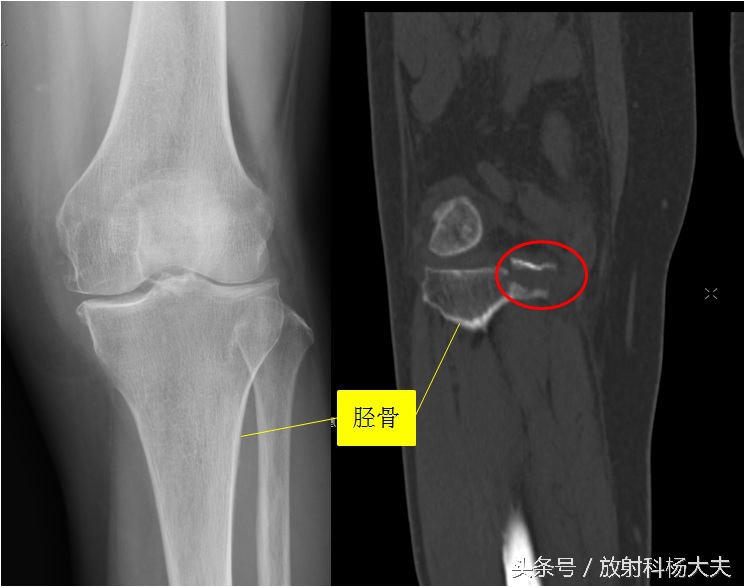

但有些骨折,X线片上就不好诊断了,需要做CT或者MRI。

比如下图的X线片,发生在胫骨平台的骨折,很难发现。但做了CT,就比较容易了,如图中的红圈。

关键的一步是谁想到建议做CT。有的时候是有经验的骨科大夫,根据体检,高度可疑胫骨平台骨折,但X线却没发现异常,此时会建议病人做CT或者MRI。有的时候是有经验的放射科大夫,读片的时候总觉得胫骨平台有的地方不对劲,再去查查体,怀疑胫骨平台骨折,会建议做CT或MRI。